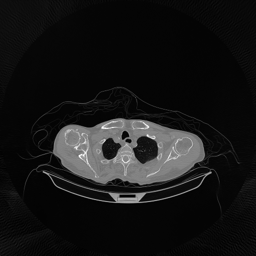

The results for simulated noisy data are shown in Fig. 2. The first and third rows display two representative slices from the test set, and the second and fourth rows present the corresponding error maps. The traditional WCE method suppresses cupping artifacts and recovers some missing anatomical structures but still shows noticeable deviations from the ground truth. Predictions from the four diffusion-based models demonstrate a markedly improved ability to restore anatomical structures. Among them, cDDPM fails to fully reconstruct the patient bed and retains residual noise in its outputs. This noise is attributable to an incomplete reverse denoising process rather than residual Poisson noise, as evidenced in our noise-free experiments (Fig. 5 in the Appendix). PatchDiffusion, diffusionGAN, and I2SB achieve similar visual quality, with I2SB producing the cleanest and most consistent reconstructions.

Quantitative results in Tab. V further confirm I2SB’s superiority over conventional deep learning methods such as FBPConvNet and Pix2pixGAN across RMSE, PSNR, and SSIM. Compared to other diffusion models—including cDDPM, PatchDiffusion, and cLDM—I2SB delivers higher image quality, while diffusionGAN achieves comparable quantitative performance. However, I2SB demonstrates a significant advantage in inference efficiency, as summarized in Tab. IV.